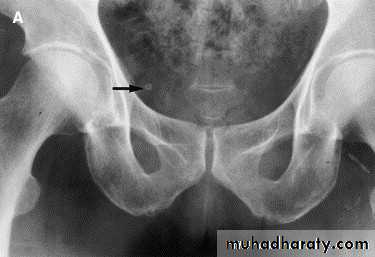

-Over 90% of calculi are radiopaque on plain films and virtually all on CT as very sensitive for detection of calculi, even those that appear radiolucent on plain film.-Most of these stones are a mixture of calcium oxalate and phosphate.

• Ddgx of stone on KUB :

• 1. Gall stone• 2. calfied LN , cartilage ,fibroid,

• 3. Phlebolith: round, lucent centre.